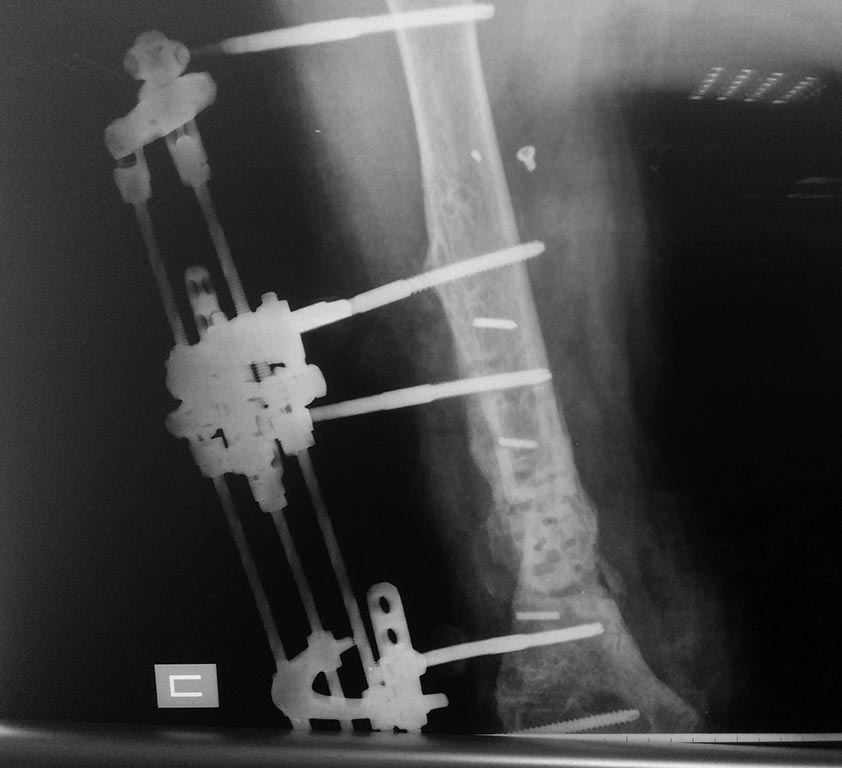

2 месяца с АВФ